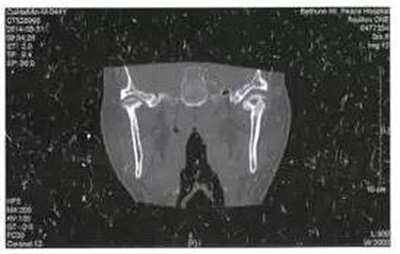

病例3,男,52歲。2月前發(fā)現(xiàn)右側(cè)上頜后牙疼痛,局部腫脹,應(yīng)用廣譜抗生素后有所減輕,但不能完全恢復(fù)。入院10天前右側(cè)面部、顳部腫痛加重,并張口受限明顯?;颊哂刑悄虿∈非抑委煵灰?guī)范。檢查右側(cè)顳部腫脹明顯,張口度10 mm,右側(cè)上頜第三磨牙深齲。CT示右側(cè)翼頜間隙及顳間隙腫脹,右側(cè)緣突骨質(zhì)破壞,在其前方形成液化區(qū)(圖3)。以間隙感染收入院后全麻下手術(shù),口外顳部和口內(nèi)右側(cè)上頜前庭溝聯(lián)合入路,暴露病變的喙突,咬骨鉗去除破壞的喙突,口內(nèi)外貫通引流。繼續(xù)抗感染治療。術(shù)后3周復(fù)查基本恢復(fù)正常,門診拔除右側(cè)上頜第三磨牙。

圖3右側(cè)喙突骨髓炎